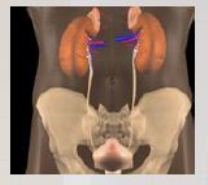

Fázová scintigrafie ledvin

Přístroj: dvouhlavá spect kamera PICKER

Radiofarmakum: 99mTc DTPA (200 MBq)

Postup vyšetření:

- poloha vleže na zádech, kamera nastavena na oblast snímání (ledvin)

- horní končetina, do které bude aplikováno radiofarmakum, je za hlavou (nesmí přijít pod přístroj, jinak dojde ke zkreslení vyšetření)

- aplikace intravenózně

- snímání 30 minut v zadní projekci